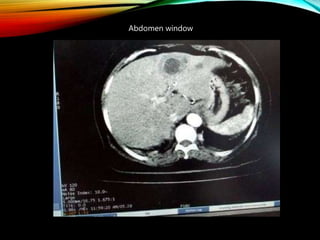

Abdomen window

-50 to -41

-40 to -31

-30 to -21

-20 to -11

-10 to 0

1-10

11-20

21-30

31-40

41-50

51-60

61-70

71-80

81-90

91-100

101-110

111-120

121-130

131-140

141-150

SOME CLINICAL WINDOW

LEVEL & WIDTH

Examination Window width Window Level

Head 80 40

Chest (mediasti) 450 40

Chest (lung) 1500 -500

Abdomen (liver) 150 60